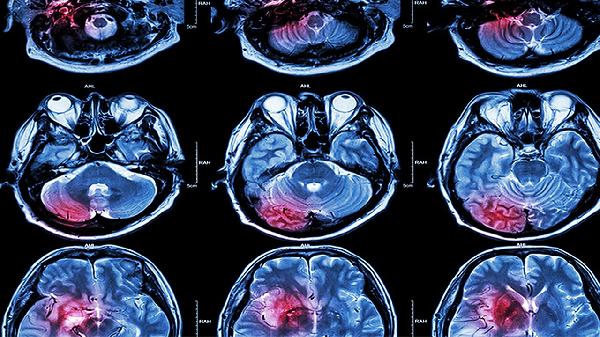

脑血栓片的主要成分包括丹参、川芎等中药材,这些成分具有活血化瘀的功效。丹参能够扩张血管,改善微循环,减少血小板聚集。川芎则有助于促进血液循环,缓解血液黏稠度增高的问题。两者协同作用可有效改善脑部供血不足的情况。